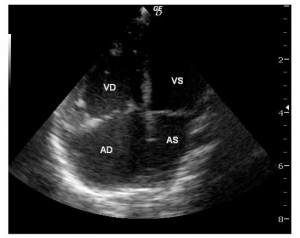

Ecocardiografia a depistat o malformaţie cardiacă congenitală simplă: defect septal interatrial (DSA) larg, tip ostium secundum, cavităţi drepte mult dilatate (atriu drept, ventricul drept, artera pulmonară), hipertensiune pulmonară (presiune pulmonară medie: 40 mmHg), defect septal interventricular muscular apical mic, insuficienţă mitrală uşoară (Figura 1, 2).

Figura 1. Ecocardiografie transtoracică incidenţă apical 4 camere: dilataţie de cavităţi drepte, defect septal interatrial tip ostium secundum. AD: atriu drept, VD: ventricul drept, AS: atriu stâng, VS: ventricul stâng.